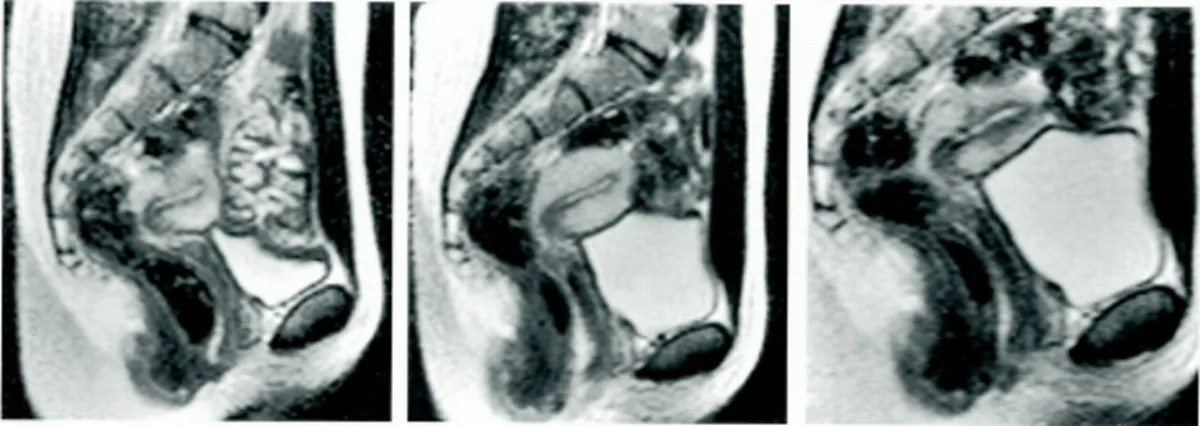

«Отримані зображення показали, що під час статевого акту в місіонерській позі статевий член має форму бумеранга, а третина його довжини складається з кореня».

Окрім анатомічних спостережень, учені звернули увагу на ще один ефект. Під час усіх зафіксованих статевих актів у МРТ у жінок швидко наповнювався сечовий міхур. У дослідженні взяли участь вісім пар і три жінки без партнерів, що зробило вибірку унікальною для медичних спостережень.

«На кожному фінальному знімку ми бачили великий, наповнений сечовий міхур, хоча більшість жінок відвідували туалет перед процедурою».

Знімок МРТ на різних етапах дослідження. Фото: bmj.com